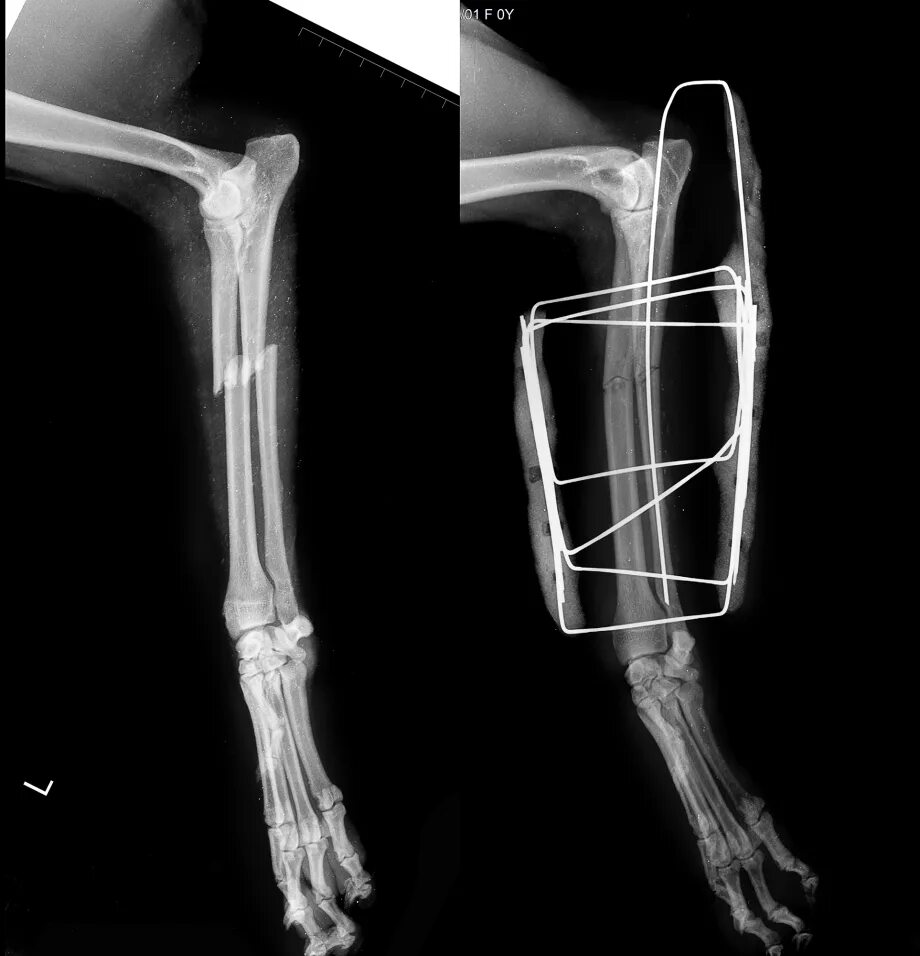

Перелом диафиза костей предплечья. остеосинтез локтевой кости аппаратом илизарова. остеосинтез диафиза лучевой кости. перелом локтевого отростка локтевой кости.

Антеградный остеосинтез стержнем перелома локтевой кости. интрамедуллярный остеосинтез предплечья. интрамедуллярный остеосинтез локтевой кости.

Остеосинтез перелома лучевой кости. остеосинтез перелома лучевой кости у собаки. внеочаговый остеосинтез. накостный остеосинтез ветеринария.